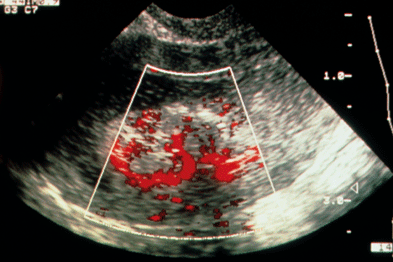

Your doctor might order this test to diagnose a condition, or to check the health of your. We are pleased to announce a new free case based urology learning program from the cleveland clinic glickman urological and kidney institute, rainbow babies and children's hospital, and university hospitals case medical center. Both kidneys appear to be ectopic and located in the pelvis, close to the ovaries (rtk= right kidney; All of our first line ultrasound scans are optional. Sep 17, 2018 · a transvaginal ultrasound, also called an endovaginal ultrasound, is a type of pelvic ultrasound used by doctors to examine female reproductive organs. Transvaginal means across or through the vagina. In this female patient, ultrasound images show an incidental finding, which is rather rare. Ultrasound is the imaging modality of choice for the female pelvis.

In this female patient, ultrasound images show an incidental finding, which is rather rare. Oct 04, 2012 · whether the female pelvis is imaged because of a suspicion of underlying gynecologic disease or as a screening examination in the asymptomatic patient, those who interpret the images should be familiar with the range of normal appearances in these organs to avoid misinterpreting expected physiologic changes as pathologic conditions and to spare. We are pleased to announce a new free case based urology learning program from the cleveland clinic glickman urological and kidney institute, rainbow babies and children's hospital, and university hospitals case medical center. It is widely available, has broad acceptance by patients as a "familiar test," and is relatively inexpensive. Jul 02, 2021 · transvaginal ultrasound is a test used to look at a woman's uterus, ovaries, tubes, cervix and pelvic area.

In this female patient, ultrasound images show an incidental finding, which is rather rare pelvic ultrasound female. Ultrasound is the imaging modality of choice for the female pelvis.